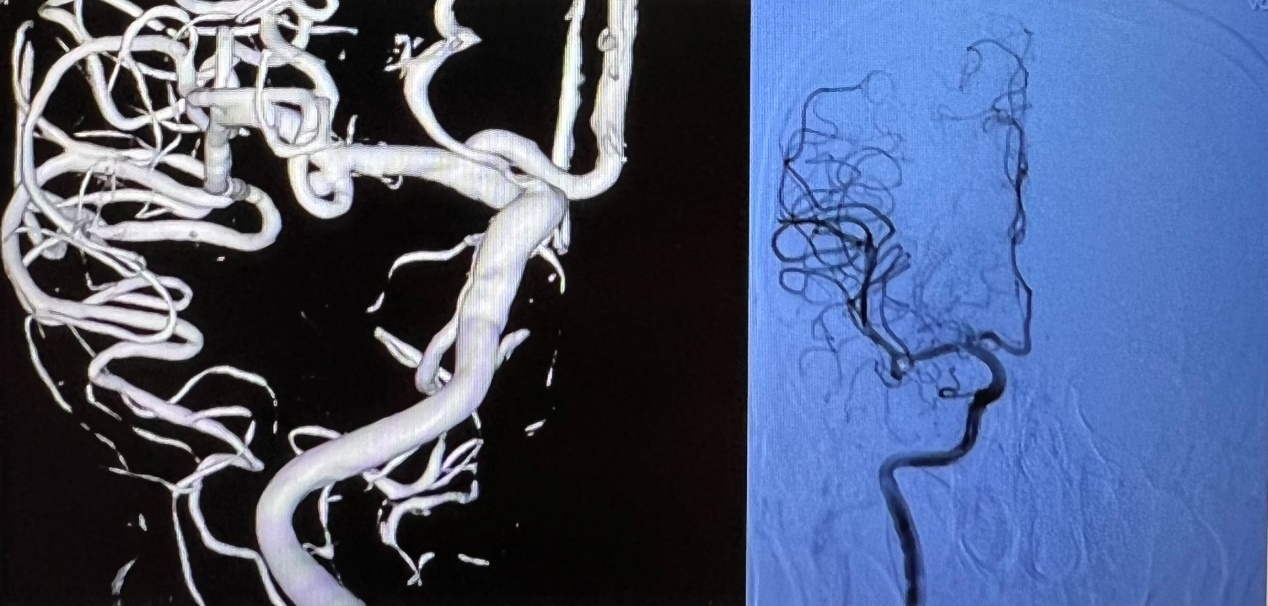

3月4日,1例自发性蛛网膜下腔出血患者紧急送入庆阳市人民医院急诊科,经检查,患者自发性蛛网膜下腔出血诊断明确,多考虑颅内动脉瘤破裂出血。庆阳市人民医院神经外科李争民主任有序协调,经过积极术前准备,在兰大二院陇东区域医疗中心帮扶庆阳市人民医院医疗队神经外科唐博副主任医师指导下,为患者行全脑血管造影,并在全麻下行“颅内动脉瘤栓塞术”,历时1个小时,手术顺利完成,患者顺利苏醒拔管。

6日,在唐博副主任医师的指导下,庆阳市人民医院神经外科又为1例前交通动脉瘤及1例颅内血管重度狭窄的患者成功实施了手术。